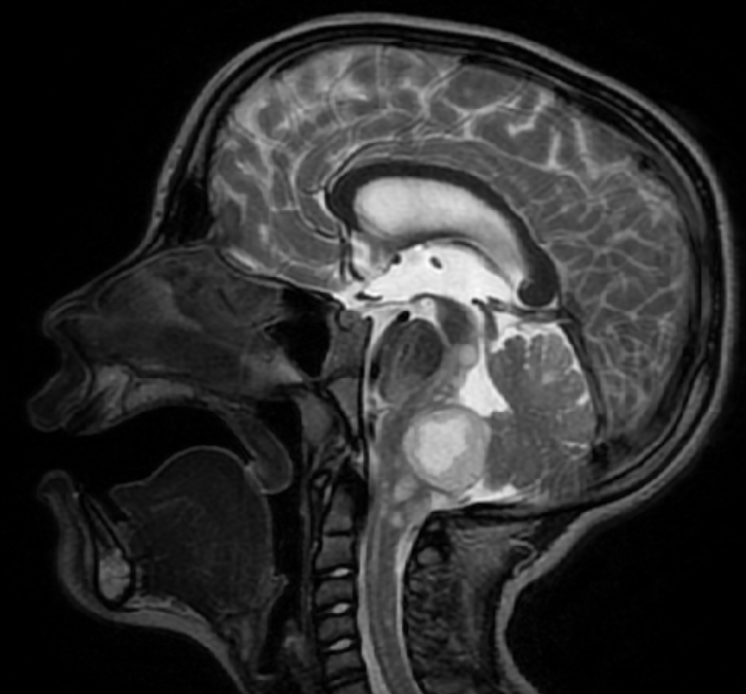

Pediatric-type, low-grade gliomas (PLGG) are the most common central nervous system (CNS) tumor in children, but in rare cases the tumors spread — known as disseminated pediatric low-grade gliomas (DPLGGs) — which leads to increased morbidity and mortality.

Researchers, led by Michael Dewan, MD, MSCI, compiled an international cohort of more than 260 DPLGG patients from 39 sites and 13 countries to study why low-grade brain tumors behave aggressively, as well as to identify the causative genetic alteration. Study findings were recently published in Neuro-Oncology.